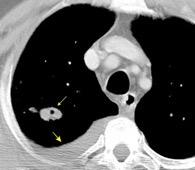

Nefrectomia derecha en 1996 por adenocarcinoma renal. Reseccion de metastasis pulmonar en LSI de carcinoma renal. Sospecha de nueva metástasis.

Granuloma de cuerpo extrano por hilo de sutura en situación cisural

Madan Ret al. Intrathoracic gossypiboma. AJR 2007/Anderson JM et al. FOREIGN BODY REACTION TO BIOMATERIALS. Semin Inmunol 2008/Okazaki M et al. Two cases of granuloma mimicking local recurrence after pulmonary segmentectomy. Journal of Cardiothoracic Surgery. 2020